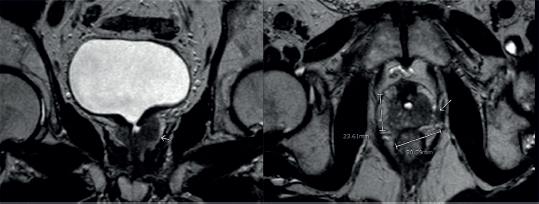

In May, 2023, the patient developed obstruction symptoms once again. Urine cytology was repeated, which was positive for neoplastic cells. He had a computed tomography (CT) scan that showed no significant lesions. He had a MRI which showed a poorly delimited tissue, hypointense in T2 sequence, which enhanced after contrast administration, surrounding the bladder neck and the prostatic urethra, showing signs of possible extra-prostatic compromise (Figure 2).

Figure 2. MRI shows an infiltrative tissue located in the left prostatic lobe. It is hypointense in the T2 sequence and enhances after endovenous contrast. It measures 30.3 × 23.6 mm.